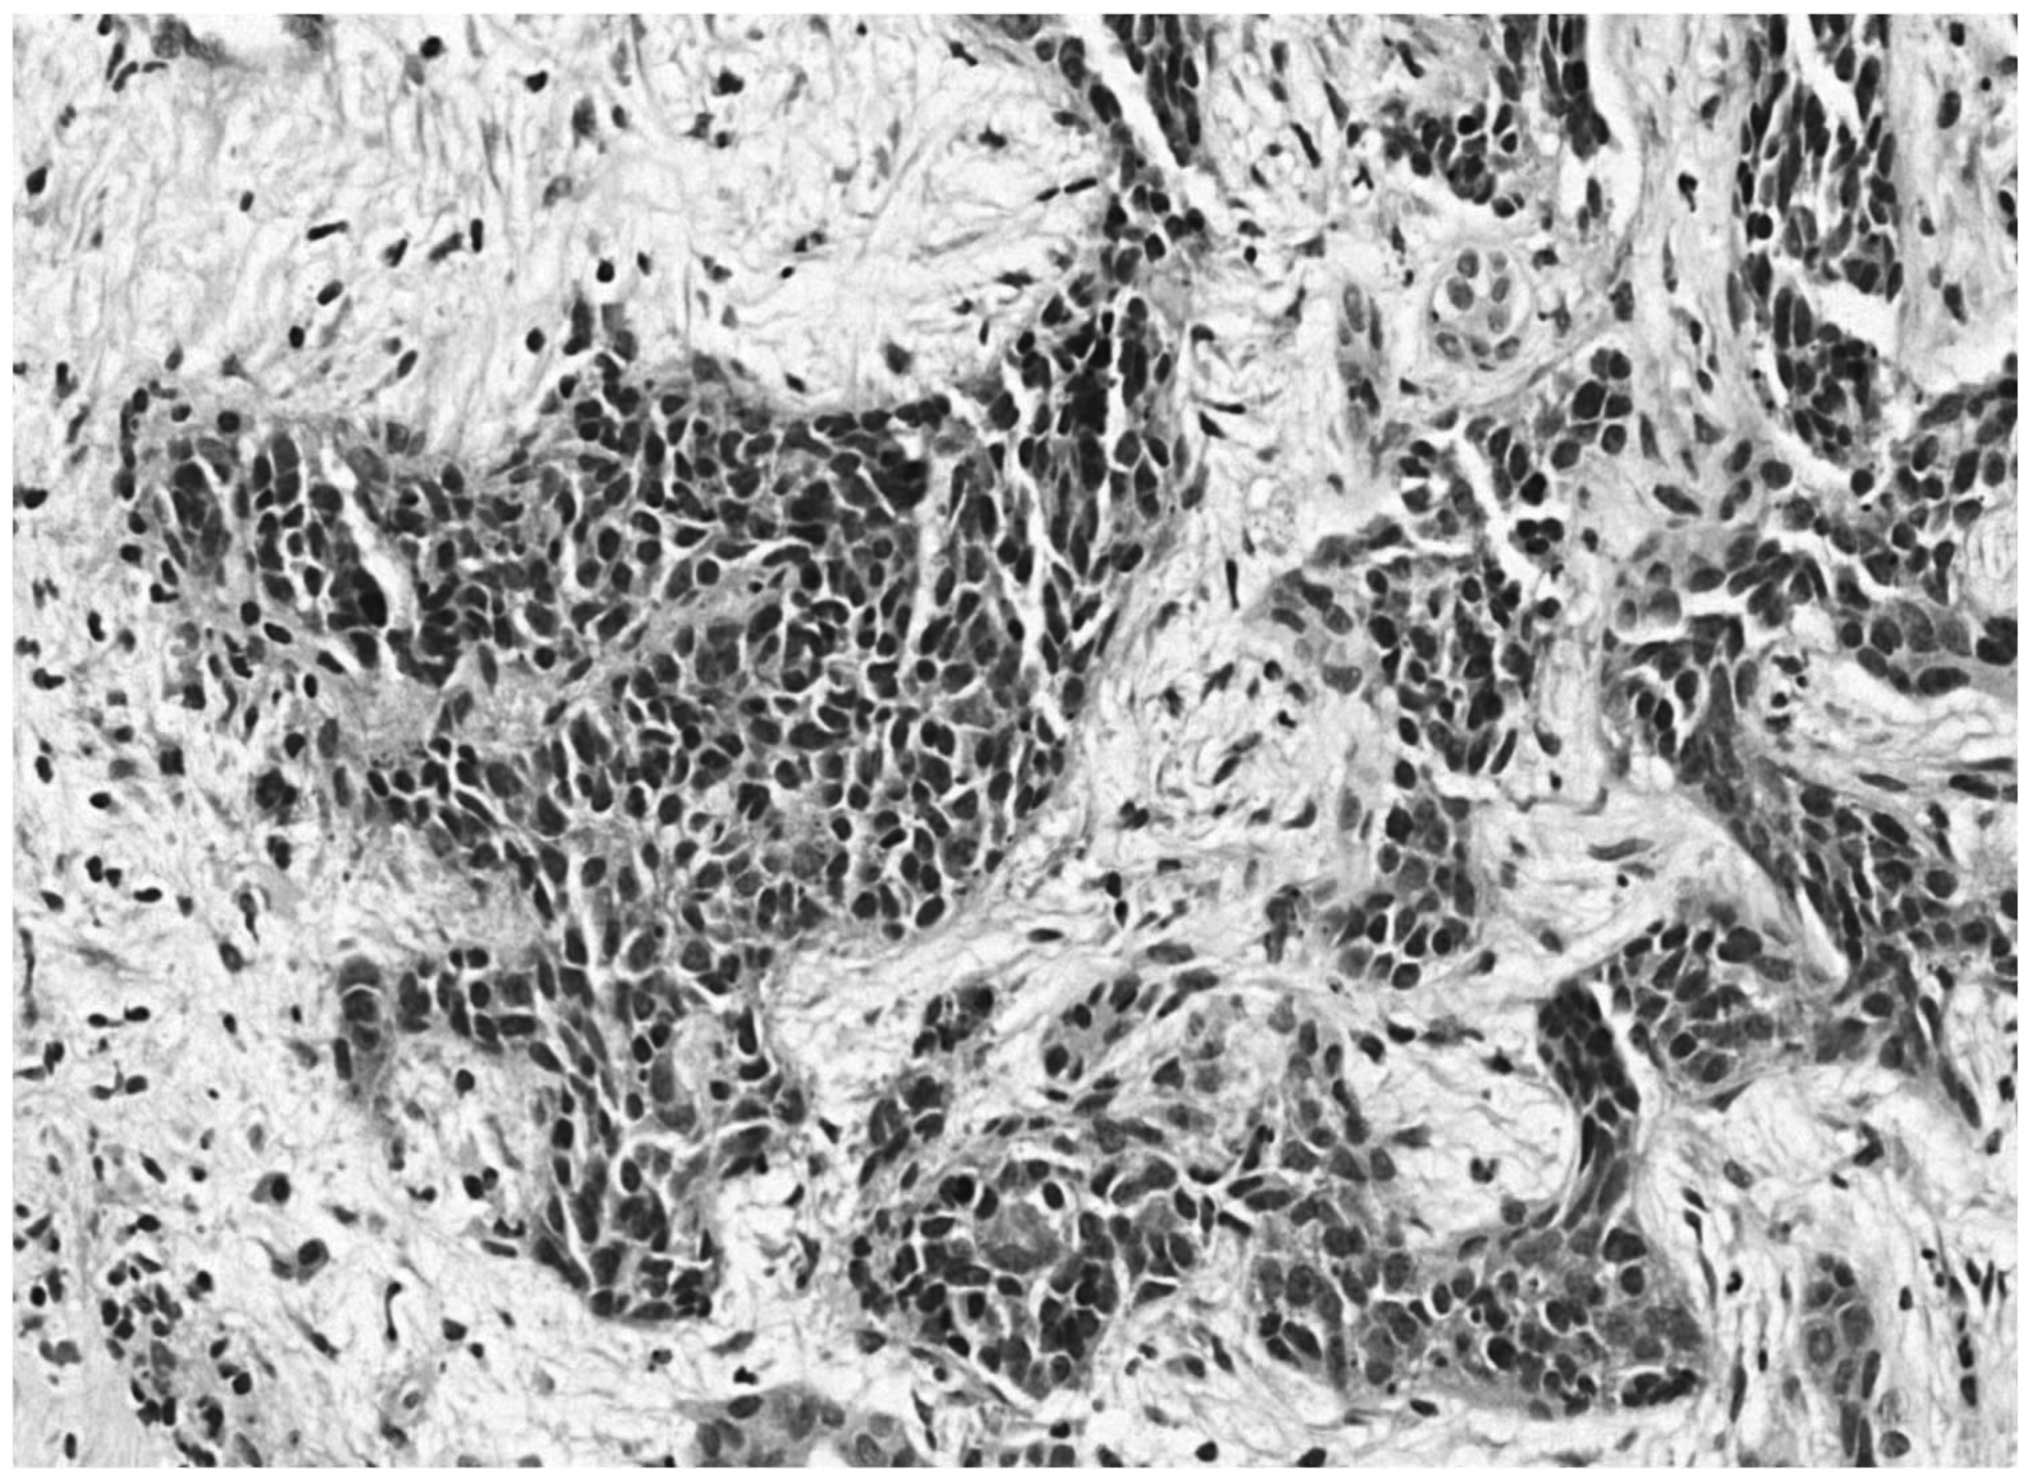

In addition, poorly delimited solid hepatic nodules with peripheral contrast enhancement were identified. The largest hepatic nodule measured 3.4 cm in diameter, and was located on segment IV. Chest CT and bone scintigraphy were normal, and an analysis of tumor markers detected 751 U/l lactate dehydrogenase (normal range, 313–618 U/l), <1.2 mU/ml β-human chorionic gonadotropin (normal range, <5.00 mU/ml), 1.24 ng/ml carcinoembryonic antigen and 2.89 ng/ml α-fetoprotein. During video laparoscopy, a large pancreatic mass, multiple liver metastases and ascites were identified. Biopsies were performed on the pancreatic mass and liver metastases, and ascites fluid was collected. Subsequent histopathological analysis determined a malignant neoplasm composed of small, blue, round cells, and immunohistochemistry identified cytokeratin and vimentin expression (with reinforcement in the paranuclear-Golgi zone), in addition to positive focal staining of desmin in a typical dot-like pattern (Fig. 6). Thus, the diagnosis of a small cell tumor was determined. Additionally, the ascites fluid was positive for neoplastic cells.